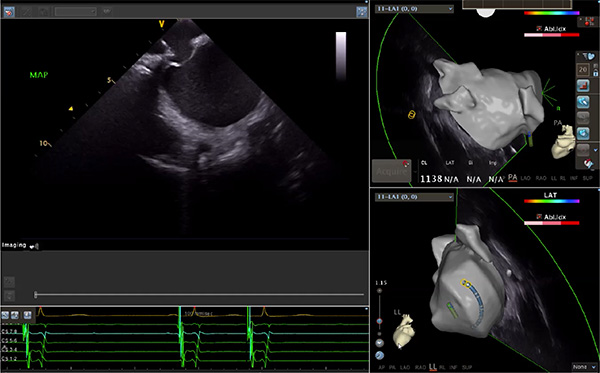

超聲心動圖技術包括常規(guī)經(jīng)胸超聲(TTE)、經(jīng)食管超聲(TEE)、心腔內(nèi)超聲(ICE)、超聲聲學造影(MCE)、三維超聲心動圖等,ICE是一種新興技術——將微型的換能器安裝在心導管的尖端,經(jīng)由外周血管輸送至心腔內(nèi)部,換能器發(fā)射聲波,對心臟及其鄰近組織進行實時高質(zhì)量成像和(或)血流動力學測定的超聲成像技術。基于不同的技術原理,心腔內(nèi)超聲導管被分為兩類:機械旋轉(zhuǎn)式超聲導管和相控陣超聲導管。目前,臨床上主要應用的是相控陣超聲導管,ICE成像通過術者旋轉(zhuǎn)導管及操縱導管手柄上的兩個旋鈕來完成。

隨著心腔內(nèi)超聲的應用更廣,性能也在逐漸優(yōu)化,已從二維成像轉(zhuǎn)變?yōu)?strong>三維成像,極大增強了引導及可視化能力。二維心腔內(nèi)超聲支持雙平面或三平面成像,可顯示兩個或三個不同的平面視圖,但醫(yī)生需將這些圖像在腦海中重新構建為三維解剖結構。三維心腔內(nèi)超聲則可直接呈現(xiàn)三維解剖結構圖,便于醫(yī)生更輕松地開展手術。按照產(chǎn)品發(fā)展方向,預計心腔內(nèi)超聲還將向更清晰、精準、多功能等方向發(fā)展。